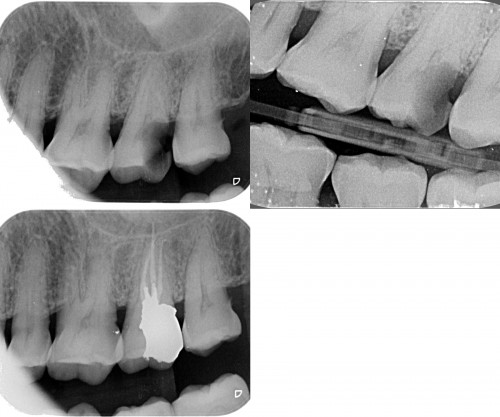

Nice cases. For the maxillary molar, did you use a saddle matrix on the second stage amalgam?

Dr. Miglani,

You demonstrate some very accomplished skills…..these are not easy restorations to do well. The enod also looks very carefully done. Keep it up!

Great execution Revathi both on the restorative and the endodontic aspects ,especially in hard to isolate areas.